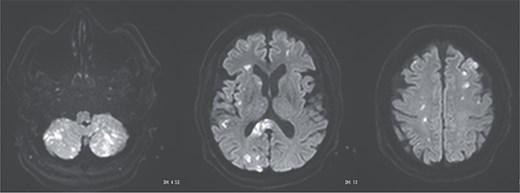

Postoperative magnetic resonance imaging showing diffuse cerebral infarctions.

A 70-year-old woman presented to the emergency department with sudden-onset chest and back pain. Contrast-enhanced CT revealed an ATAAD extending from the ascending aorta to the bilateral common iliac arteries. The primary entry tear extended from the ascending aorta into the aortic arch, and the false lumen remained patent throughout its entire peripheral extent (Fig. 1). Both renal arteries originated from the true lumen, and there was no malperfusion. Vital signs were stable, and the patient was not in shock. The patient underwent emergency total arch replacement with FET implantation using a 27 × 90 mm FROZENIX four-branched graft (Japan Lifeline Co., Ltd, Tokyo, Japan). The procedure was completed in 7 h and 6 min without intraoperative complications. Postoperatively, urine output declined markedly. Serum creatinine increased from a baseline of 0.81 to 2.61 mg/dl on postoperative Day 1. Diuretics failed to improve urine output, and renal replacement therapy was initiated. Contrast-enhanced CT on postoperative Day 2 showed no signs of renal malperfusion. Although the renal medulla exhibited normal enhancement, a diffuse non-enhancing area throughout the renal cortex—referred to as the “reverse rim sign”—was observed, consistent with RCN (Fig. 2). Thrombosis of the false lumen in the descending thoracic and thoracoabdominal aorta had progressed (Fig. 3). The patient developed persistent coagulopathy, with sustained hypofibrinogenemia and thrombocytopenia. On postoperative Day 2, the platelet count was 4.1 × 104/μl, D-dimer 13.5 μg/ml, and PT-INR 1.54, yielding an International Society on Thrombosis and Hemostasis DIC score of 6, consistent with overt DIC. Anticoagulation therapy with heparin and warfarin was administered. Ultimately, by postoperative Day 50, a total of 36 units of fresh frozen plasma and 100 units of platelets had been transfused; however, coagulation parameters gradually normalized thereafter, and no further transfusions were required (Fig. 4). A follow-up CT on postoperative Day 21 demonstrated further remodeling of the thrombosed false lumen. Brain magnetic resonance imaging performed on postoperative Day 9 to investigate delayed emergence revealed multiple scattered small acute ischemic infarctions involving the cerebellum, brainstem, and cerebral cortex (Fig. 5). These were not attributed to large-vessel occlusion but rather to systemic microthrombotic emboli. Despite supportive care, renal function did not recover, and maintenance dialysis was initiated. The patient was transferred to another hospital on postoperative Day 182.

Postoperative DIC following ATAAD repair can compromise major organ function, including the kidneys and brain. Prompt diagnosis and appropriate anticoagulation may be essential to improve patient outcomes. Although recombinant thrombomodulin has been reported to be effective in DIC, its use may be contraindicated in cases with high bleeding risk [7]. In our case, the presence of widespread cerebral infarctions raised concern for hemorrhagic transformation; thus, thrombomodulin was not administered.